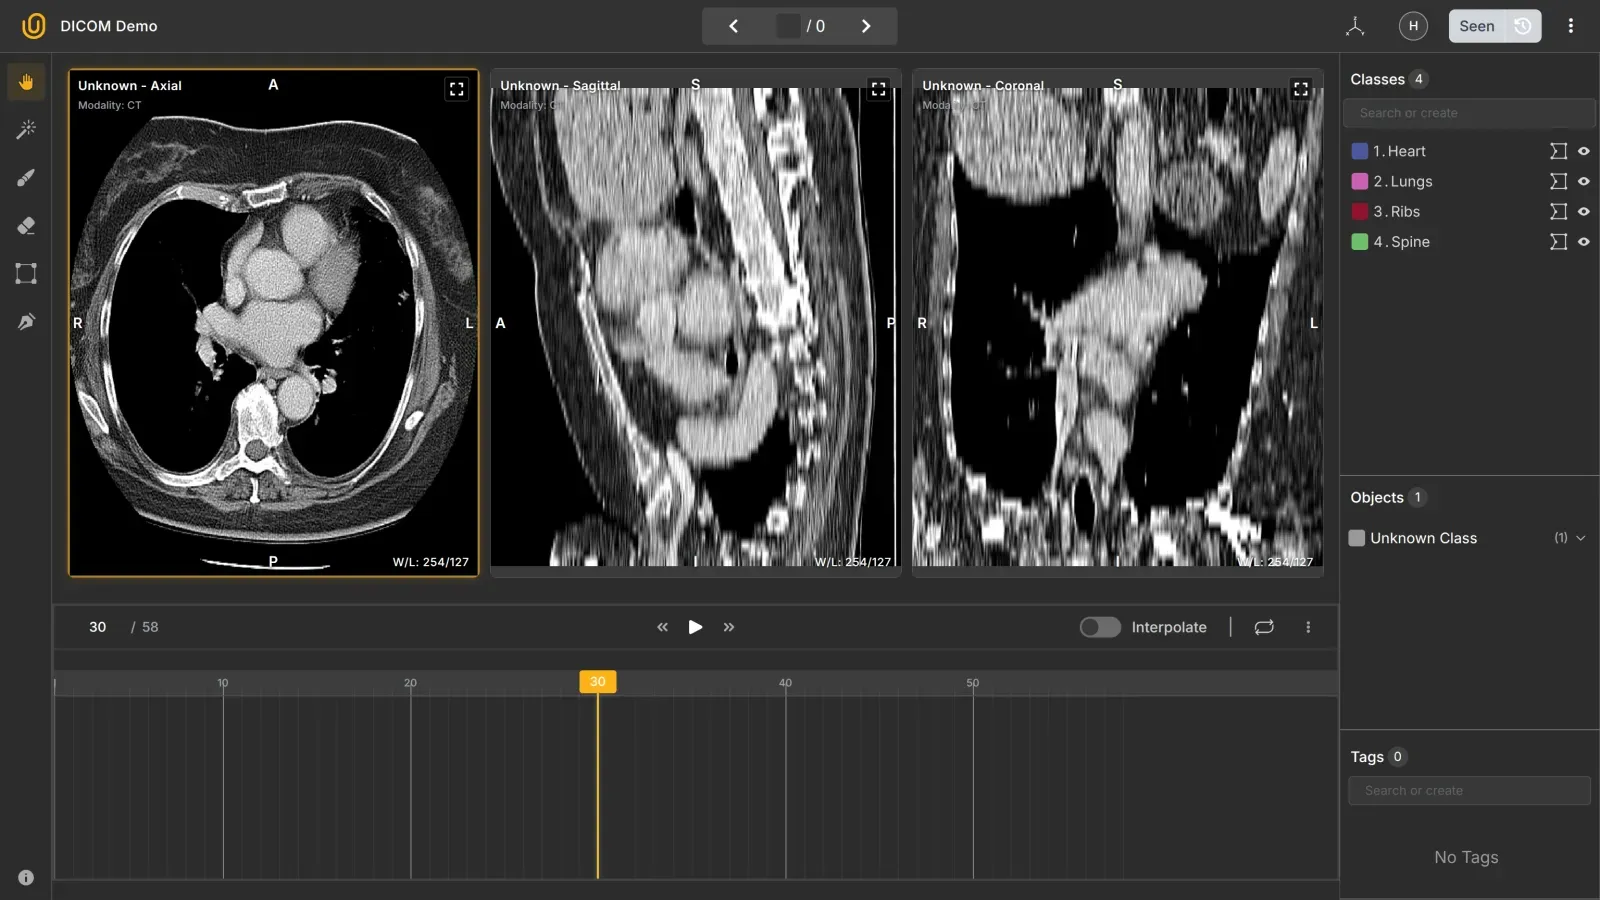

Unitlab AI is built for fast, accurate data annotation across domains, including medical imaging. You get advanced segmentation tools, batch auto-annotation, and a smooth UI for data labeling, project management, and dataset management.

You can load CTs, MRIs, and X-rays, annotate slices, and apply AI-based interpolation suggestions to speed up work. Team workflows help radiologists review, comment, and correct masks.

Why use it:

- Fast medical labeling with automation

- Smooth handling of large datasets with version control and import/export features

- Accurate segmentation tools

- Strong real-time collaboration between annotators and reviewers

- Easy model integration with the platform

Pricing: Freemium + Transparent, SaaS plans listed on the website. You can try the DICOM annotation tool in under 5 minutes for free.

Best for: Teams that want scale, speed, and detailed control over their datasets.